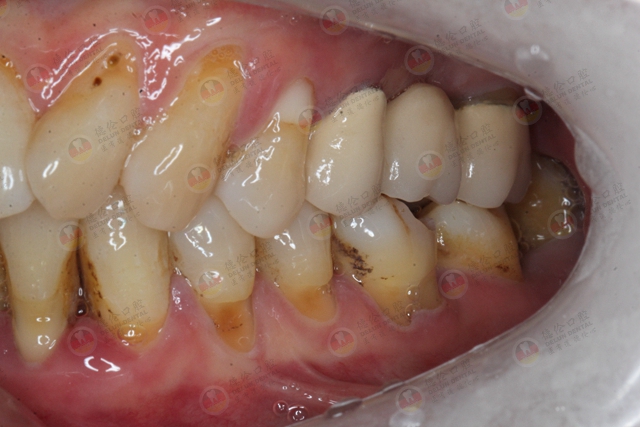

4、牙齿变长、牙缝变大

在炎症的作用下,牙周组织被破坏,类似树根的“周围土壤”出现了流失,导致牙根裸露,牙齿变长,牙缝变大。